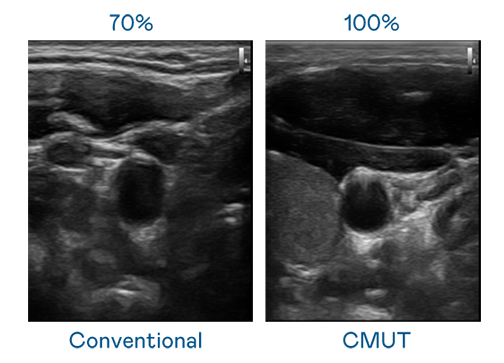

CMUT 技术是一种用电容式微机电元件来产生超音波讯号的技术。与传统 PZT 压电式技术相比,CMUT 频宽增加 30%,更宽频的超音波讯号让影像解析度大幅提升,是实现高影像品质医疗超音波扫描、促进精准医疗发展的关键技术。

大频宽带来超清晰影像

超音波影像的解析度高低,首先取决于探头能发出的讯号频宽。果冻传媒原创 CMUT 可提供高清晰的超音波讯号,提供高频宽、高灵敏度、影像纹理细节更高的超音波影像,协助医护人员缩短影像判读时间及利用精准的医疗影像进行诊断。